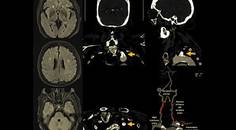

Ischemic Complications from a Facial Lipofilling Procedure

Sanaz Rezaei, MD; Fatemeh Talebi, MDSanaz Rezaei, MD; Fatemeh Talebi, MD - Stroke